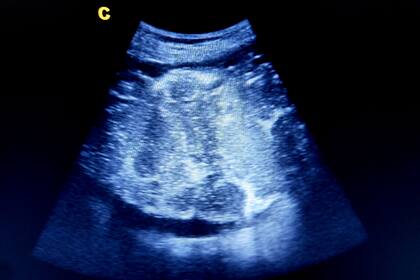

El tejido normal de la placenta tiene un tono rojizo saludable y esponjoso. Los especímenes que estudiaron estaban rígidos, con decoloraciones oscuras de tejido muerto. Aunque otras infecciones pueden dañar la placenta en ocasiones, Schwartz dijo que nunca había visto que causaran una destrucción tan consistente y extensa.

La placenta es un órgano temporario que se forma y se adhiere al útero durante el embarazo. Se conecta con el cordón umbilical, proporcionando oxígeno y alimento del torrente sanguíneo de la madre.

Es probable que el virus llegara a la placenta a través del torrente sanguíneo, adhiriéndose a las células susceptibles y provocando depósitos de proteínas y una forma inusual de inflamación que bloqueó el flujo sanguíneo y el oxígeno. Esto, a su vez, provocó la muerte del tejido de la placenta y la asfixia, según los investigadores.